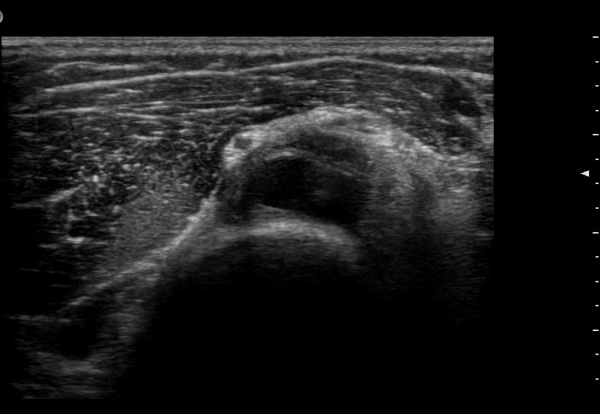

ŽÃËÀÚ¸¦ ¸»´ÜÀ¸·Î À̵¿ÇÏ´Ï ¿ä°ñµÎ ºÎÀ§¿¡¼­ Àú¿¡ÄÚ ³¶Á¾ÀÌ Èİñ°£½Å°æºÐÁö¸¦ Ç¥ÃþÀ¸·Î

ÀüÀ§½Ã۰í ÀÖ´Ù(±×¸² 2, 3,)

Á¾´Ü¸é°Ë»ç¿¡¼­ Àú¿¡ÄÚ ³¶Á¾ÀÇ Ç¥Ãþ¿¡¼­ Èİñ°£½Å°æºÐÁö°¡ ÀüÀ§µÇ¾î °üÂûµÈ´Ù(±×¸² 4, 5, 6).